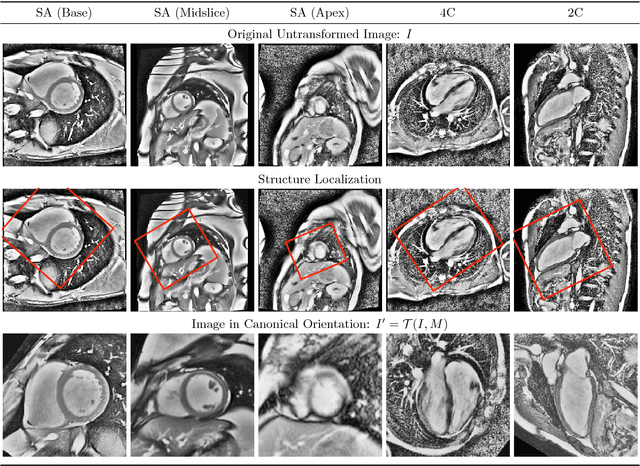

Pixelwise segmentation of the left ventricular (LV) myocardium and the four cardiac chambers in 2-D steady state free precession (SSFP) cine sequences is an essential preprocessing step for a wide range of analyses. Variability in contrast, appearance, orientation, and placement of the heart between patients, clinical views, scanners, and protocols makes fully automatic semantic segmentation a notoriously difficult problem. Here, we present ${\Omega}$-Net (Omega-Net): a novel convolutional neural network (CNN) architecture for simultaneous localization, transformation into a canonical orientation, and semantic segmentation. First, an initial segmentation is performed on the input image, second, the features learned during this initial segmentation are used to predict the parameters needed to transform the input image into a canonical orientation, and third, a final segmentation is performed on the transformed image. In this work, ${\Omega}$-Nets of varying depths were trained to detect five foreground classes in any of three clinical views (short axis, SA, four-chamber, 4C, two-chamber, 2C), without prior knowledge of the view being segmented. The architecture was trained on a cohort of patients with hypertrophic cardiomyopathy and healthy control subjects. Network performance as measured by weighted foreground intersection-over-union (IoU) was substantially improved in the best-performing ${\Omega}$- Net compared with U-Net segmentation without localization or orientation. In addition, {\Omega}-Net was retrained from scratch on the 2017 MICCAI ACDC dataset, and achieves state-of-the-art results on the LV and RV bloodpools, and performed slightly worse in segmentation of the LV myocardium. We conclude this architecture represents a substantive advancement over prior approaches, with implications for biomedical image segmentation more generally.